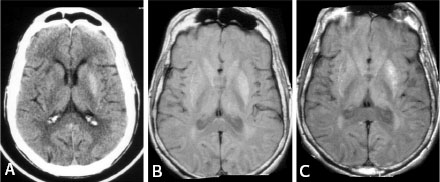

This is a patient 70 years old, male, with previous history

of diabetes mellitus type II, who presented in August 2003 with hemichorea

and hyperglycemia. Final diagnosis was hemichorea induced by non-ketotic

hyperglycemia. Striatal hyperdensity is seen on CT and T1-hyperintensity is

present on MRI.